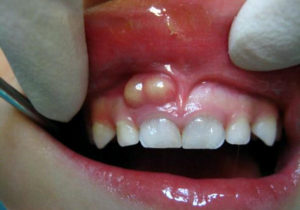

Періостит має яскраво виражену характерну симптоматику. Дитина скаржиться на біль, що підсилюється при натисненні або жуванні, і відмовляється від їжі. Флюс виглядає як шишка на десні, яка являє собою гнійний вогнище (див. на фото вище). В залежності від локалізації спостерігається набряк близько розташованих тканин – припухають щока, підборіддя, область під оком чи біля вуха.

Періостит має характерну симптоматику, тому складнощів з діагностикою зазвичай не викликає. Захворювання визначається в ході огляду дитини лікарем-стоматологом – флюс видають червона набрякла десна, біль при натисканні і появу кульки з гноєм. Іноді додатково призначаються лабораторні дослідження крові або рентген для визначення ступеня поширення інфекції та виявлення причини запального процесу.